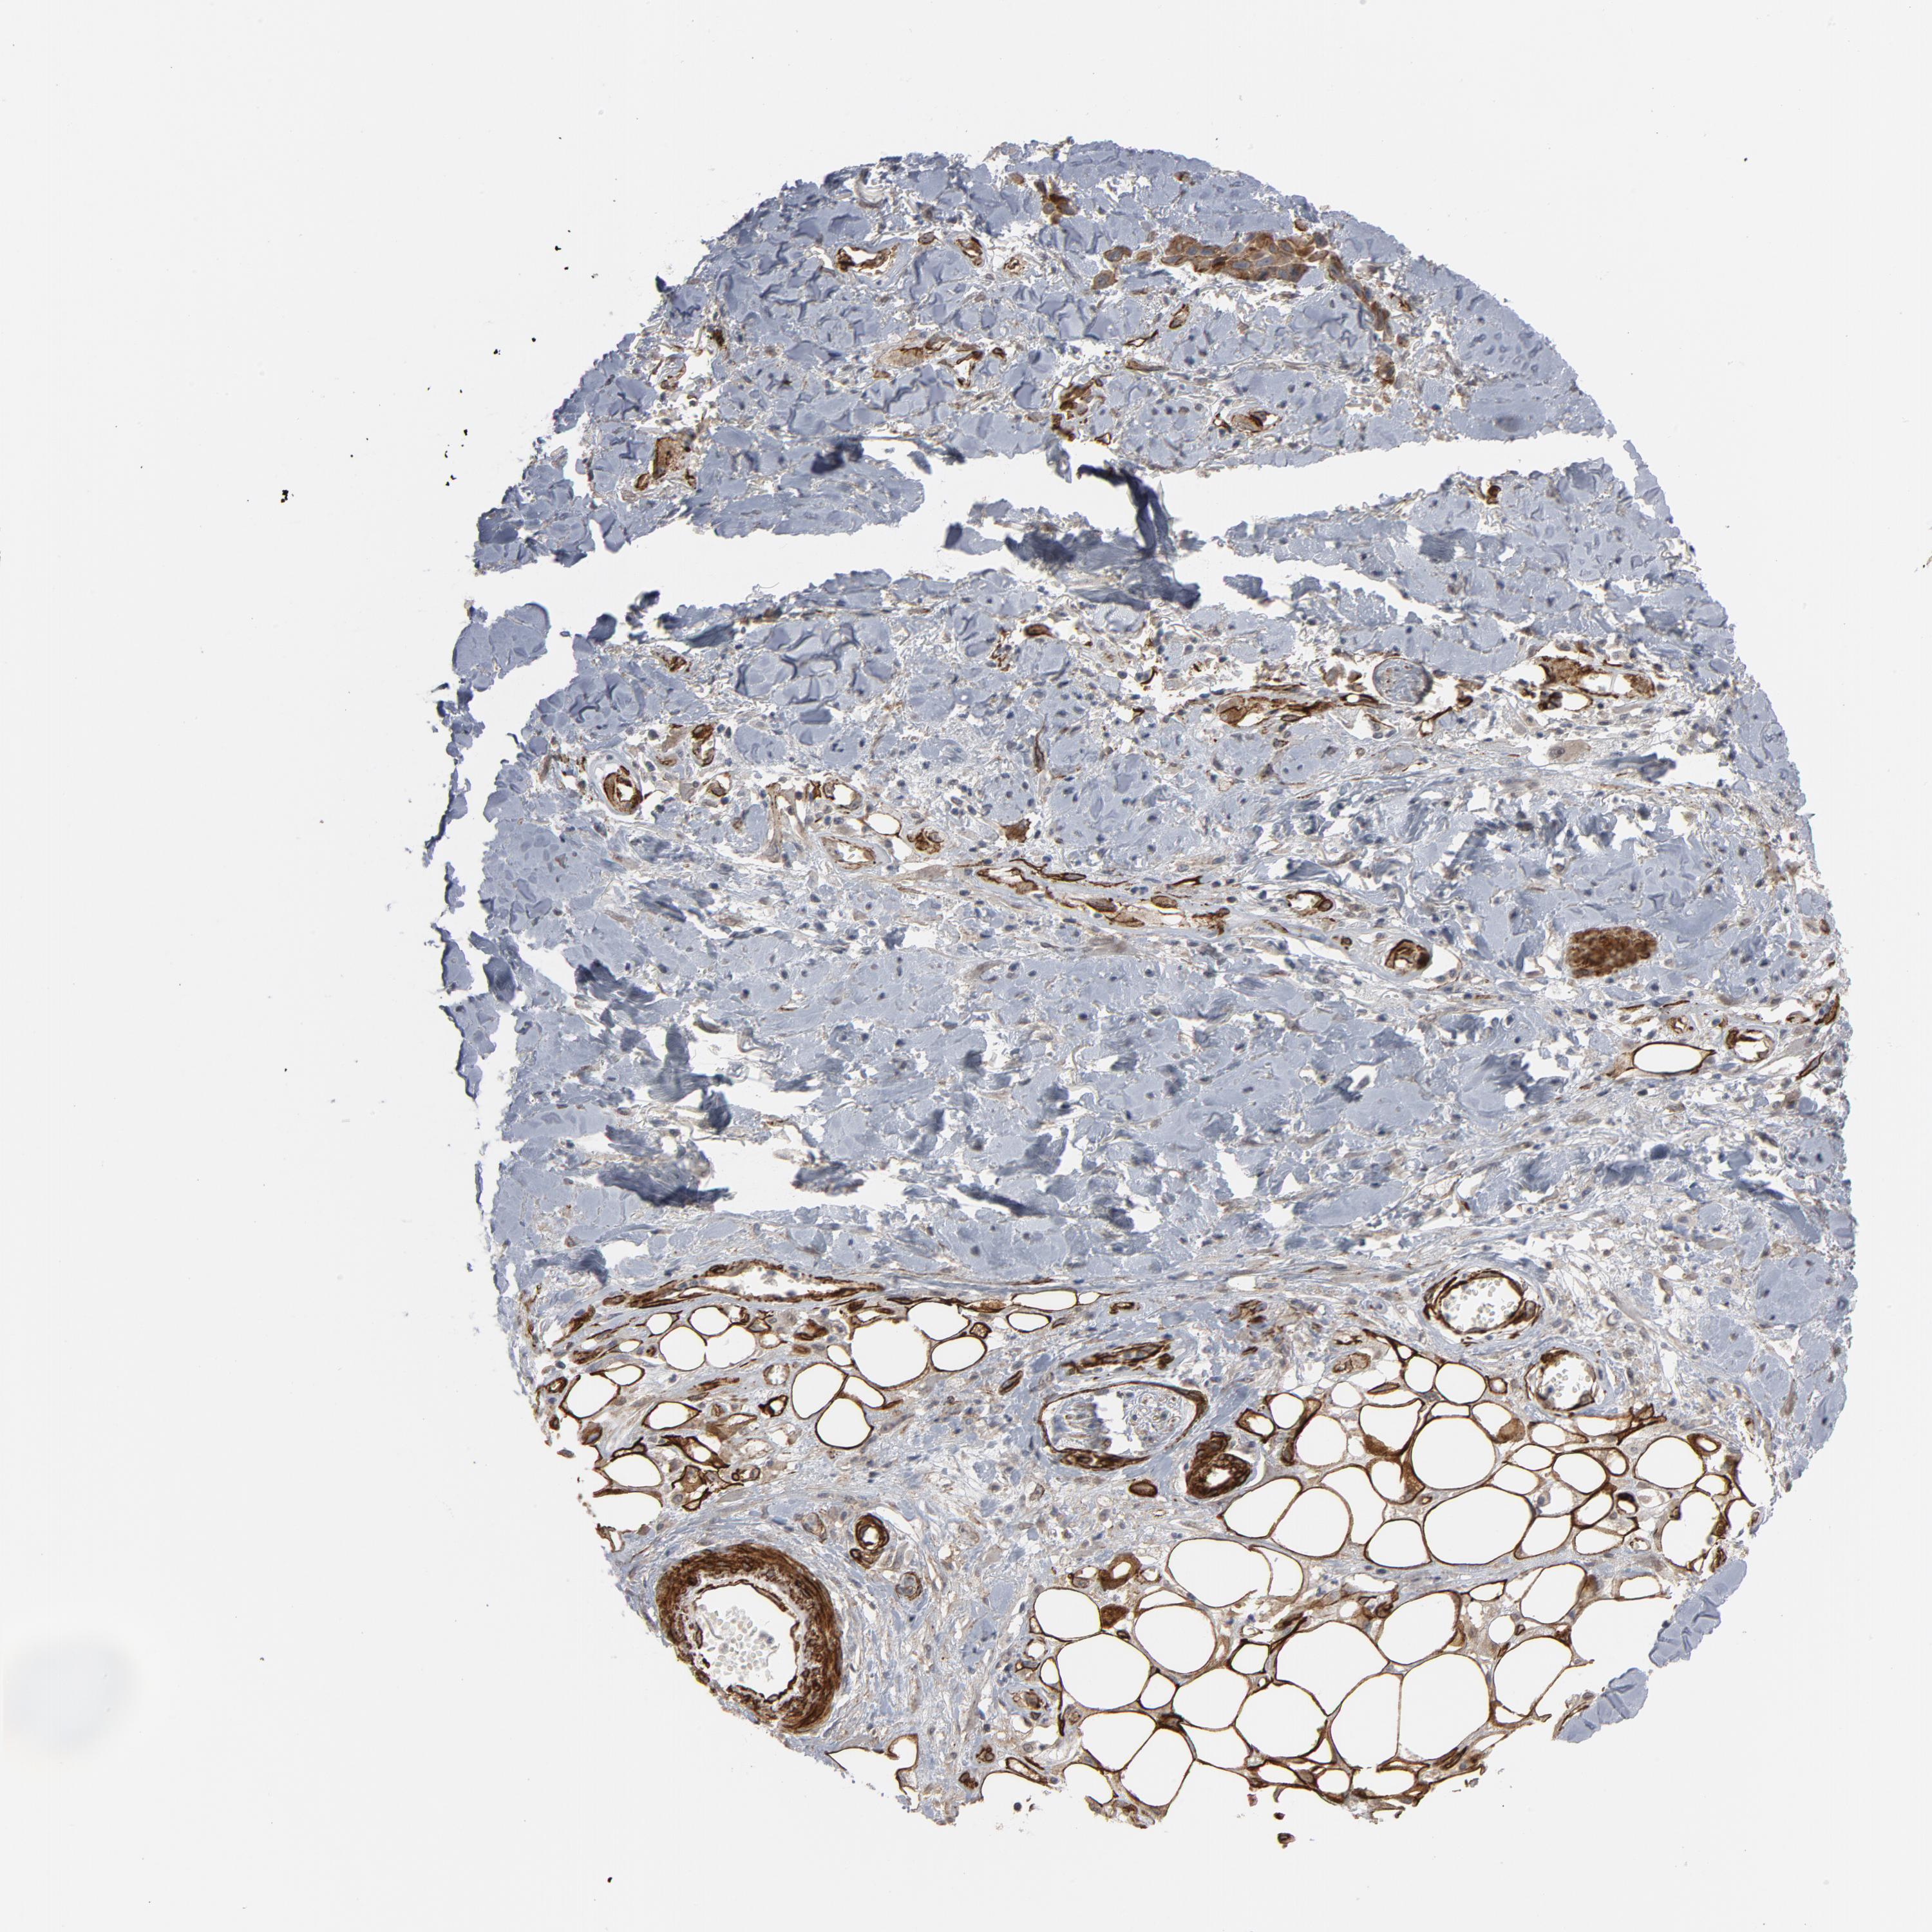

SKIN CANCER - Protein expressioni

A mouse-over function shows sample information and annotation data. Click on an image to view it in a full screen mode. Samples can be filtered based on level of antibody staining by selecting one or several of the following categories: high, medium, low and not detected. The assay and annotation is described here.

Antibody stainingi

Antibody staining in the annotated cell types in the current human tissue is reported as not detected, low, medium, or high, based on conventional immunohistochemistry profiling in selected tissues. This score is based on the combination of the staining intensity and fraction of stained cells.

Each image is clickable and will lead to virtual microscopy that enables deeper exploration of all samples and also displays staining intensity scores, fraction scores and subcellular localization as well as patient and tissue information for each sample.

Antibody HPA003534

Squamous cell carcinoma, NOS

Basal cell carcinoma

Squamous cell carcinoma in situ, NOS

Squamous cell carcinoma, metastatic, NOS

Adnexal tumor, benign